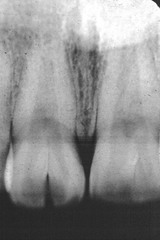

-asymptomatic radiolucency associated with the root of a NONVITAL tooth